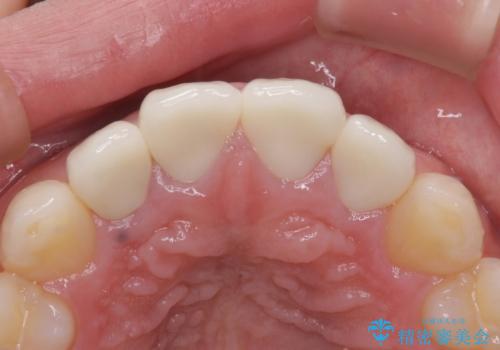

根管治療のやり直しは希望されなかったため、土台のやり替えと、より自然なオールセラミッククラウンへのやり替えを行いました。

自然できれなオールセラミッククラウンになり、とても満足されました。